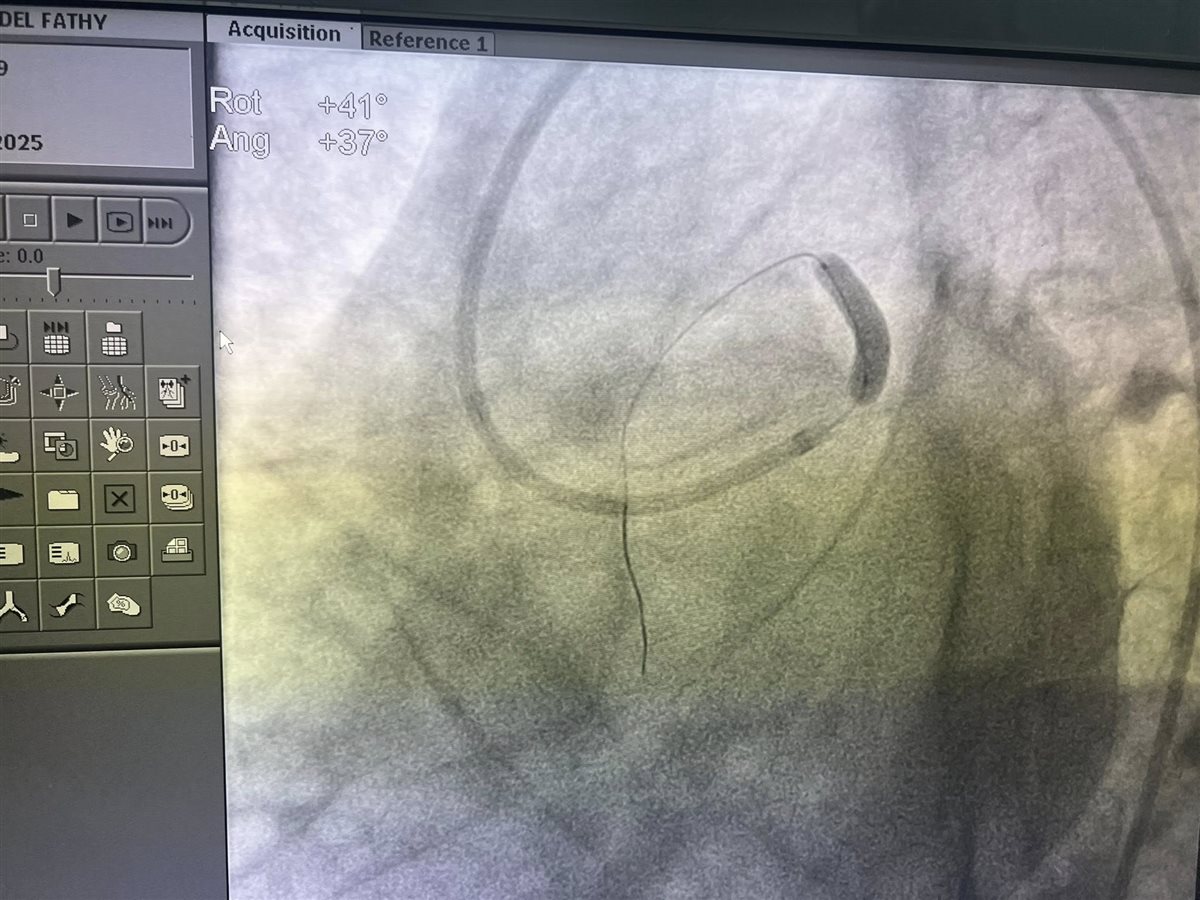

وأضاف رئيس قسم القلب بمستشفى الزيتون التخصصي: الحالة الرابعة عشرة كانت لشاب بدأ يعاني من صعوبة في التنفس منذ أربعة أيام، وتلقى علاجًا مدرًا للبول في مستشفى أخرى، مما أدى إلى نقص شديد في مستوى البوتاسيوم في الدم، متابعًا: وعند وصوله إلينا، كان يعاني من ارتشاح شديد في الغشاء التاموري أدى إلى هبوط حاد في كافة العلامات الحيوية، وتم إنقاذه بعد إجراء سحب طارئ لحوالي 600 مل من السائل المتجمع حول القلب.